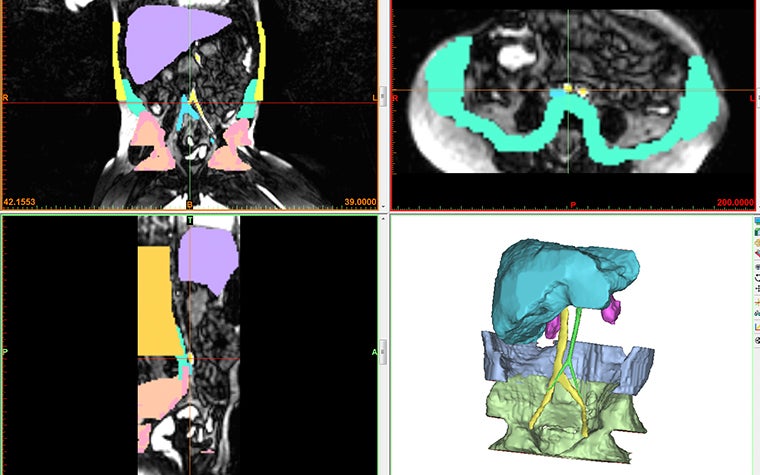

Lucy’s abdomen was scanned and segmented into Materialise Mimics Core and recreated in 3D along with crucial parts of her anatomy, such as the aorta, the coeliac axis, the superior mesenteric artery, the common iliac arteries, the inferior vena cava, the common iliac veins, the pelvic bones, the lateral abdominal wall, and the inferior margin. Then her father’s kidney was also scanned and turned into a 3D model. Finally, both models were sent off to the 3D printer at Guy’s and St. Thomas’ 3D printing facility. The hospital works with PolyJet technology, which allows them to create 3D medical models in different materials to replicate the different mechanical properties of different sorts of tissues.